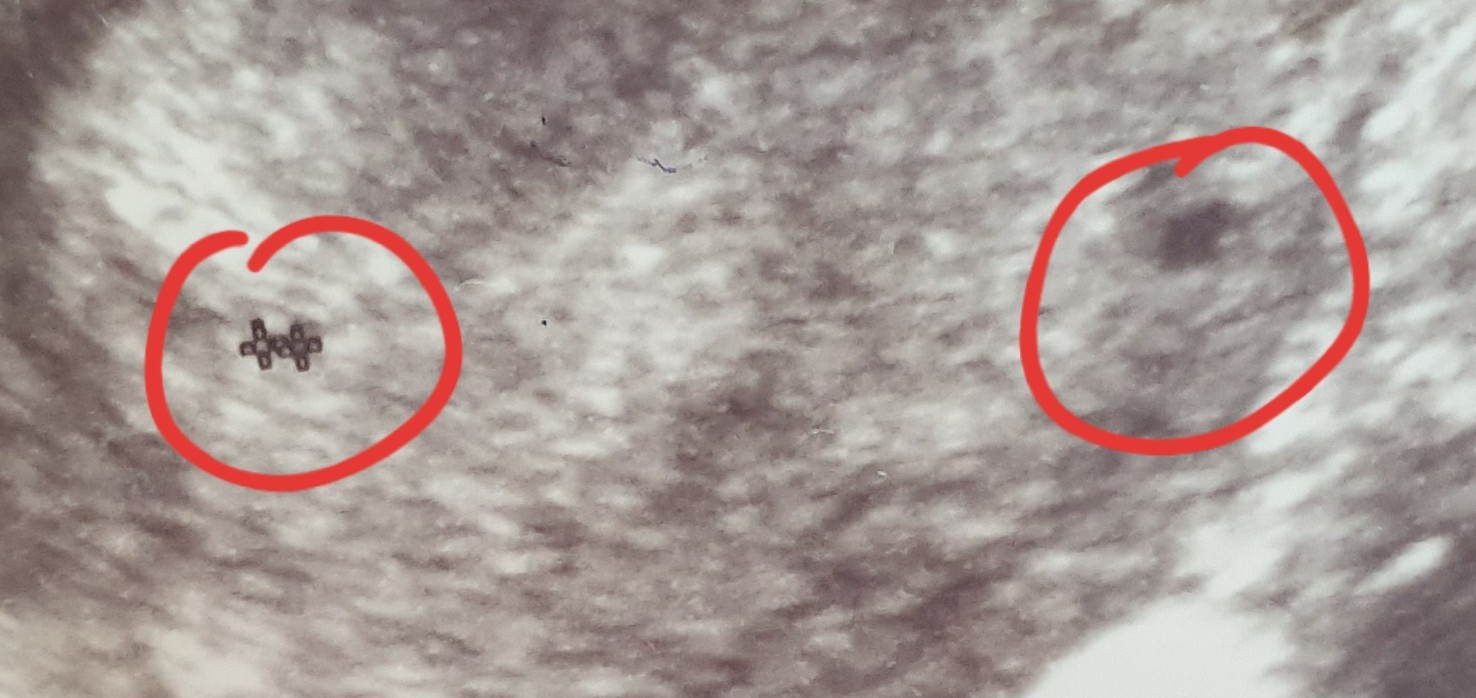

Hej Mamusie bliźniaków. Pierwsze usgz 5 tyg ciazy drugie z 6 tygodnia ciazy. Czy to są 2 pęcherzyki ciążowe? Czy mam jakieś urojenia? Lekarz nic nie mówił Ale za to przepisał duphastpn i luteine A przy pierwszej ciazy tylko luteine. Dziękuję Wam za odpowiedź. Może pamiętacie swoje usg z początków. :D

Załączniki

• 20210512_155147.jpg

20210512_155147.jpg

176,2 KB · Wyświetleń: 114